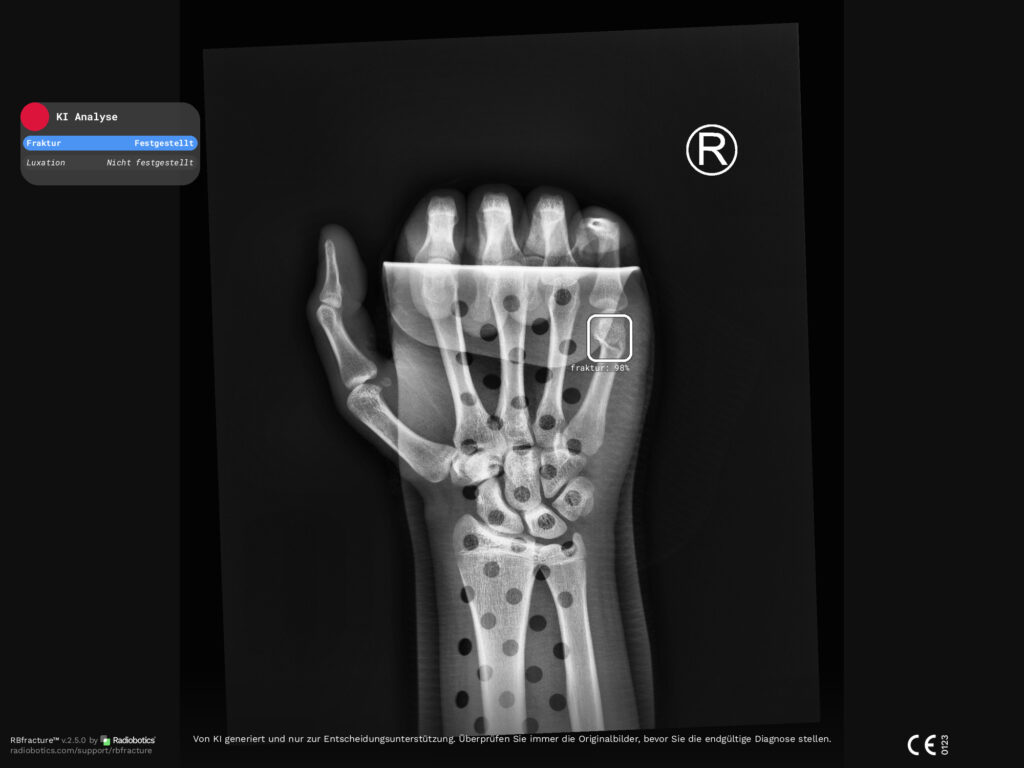

Die Main-Kinzig-Kliniken haben eine moderne, KI-gestützte Software zur automatisierten Erkennung von Knochenbrüchen (Frakturen) und Gelenkverrenkungen (Luxationen) eingeführt. Das neue System analysiert seit Kurzem jede Röntgenaufnahme des Skeletts innerhalb von nur zwei bis drei Minuten nach ihrer Erstellung und markiert verdächtige Bereiche direkt im Bild.

Die Software erkennt potenzielle Frakturen mit hoher Sensitivität, übersieht also vergleichsweise wenige mögliche Verletzungen. Gleichzeitig ist die Spezifität noch begrenzt, sodass manche auffälligen Befunde sich im Nachgang nicht als Brüche herausstellen.

„Die KI bietet uns einen wertvollen zusätzlichen Blick auf jede Röntgenaufnahme. Sie erkennt mögliche Frakturen sehr zuverlässig und hilft dabei, auch kleinste oder schwer sichtbare Verletzungen frühzeitig zu identifizieren. Gleichzeitig bleibt klar: Die abschließende Diagnose trifft immer der erfahrene Radiologe. Die Kombination aus modernster Technik und fachärztlicher Expertise erhöht die Sicherheit für unsere Patientinnen und Patienten deutlich“, erklärt PD Dr. med. Markus Zimmermann, Chefarzt der Klinik für Diagnostische und Interventionelle Radiologie.

Bildnachweis: Hand-Fraktur_©RBfracture™-by-Radiobotics